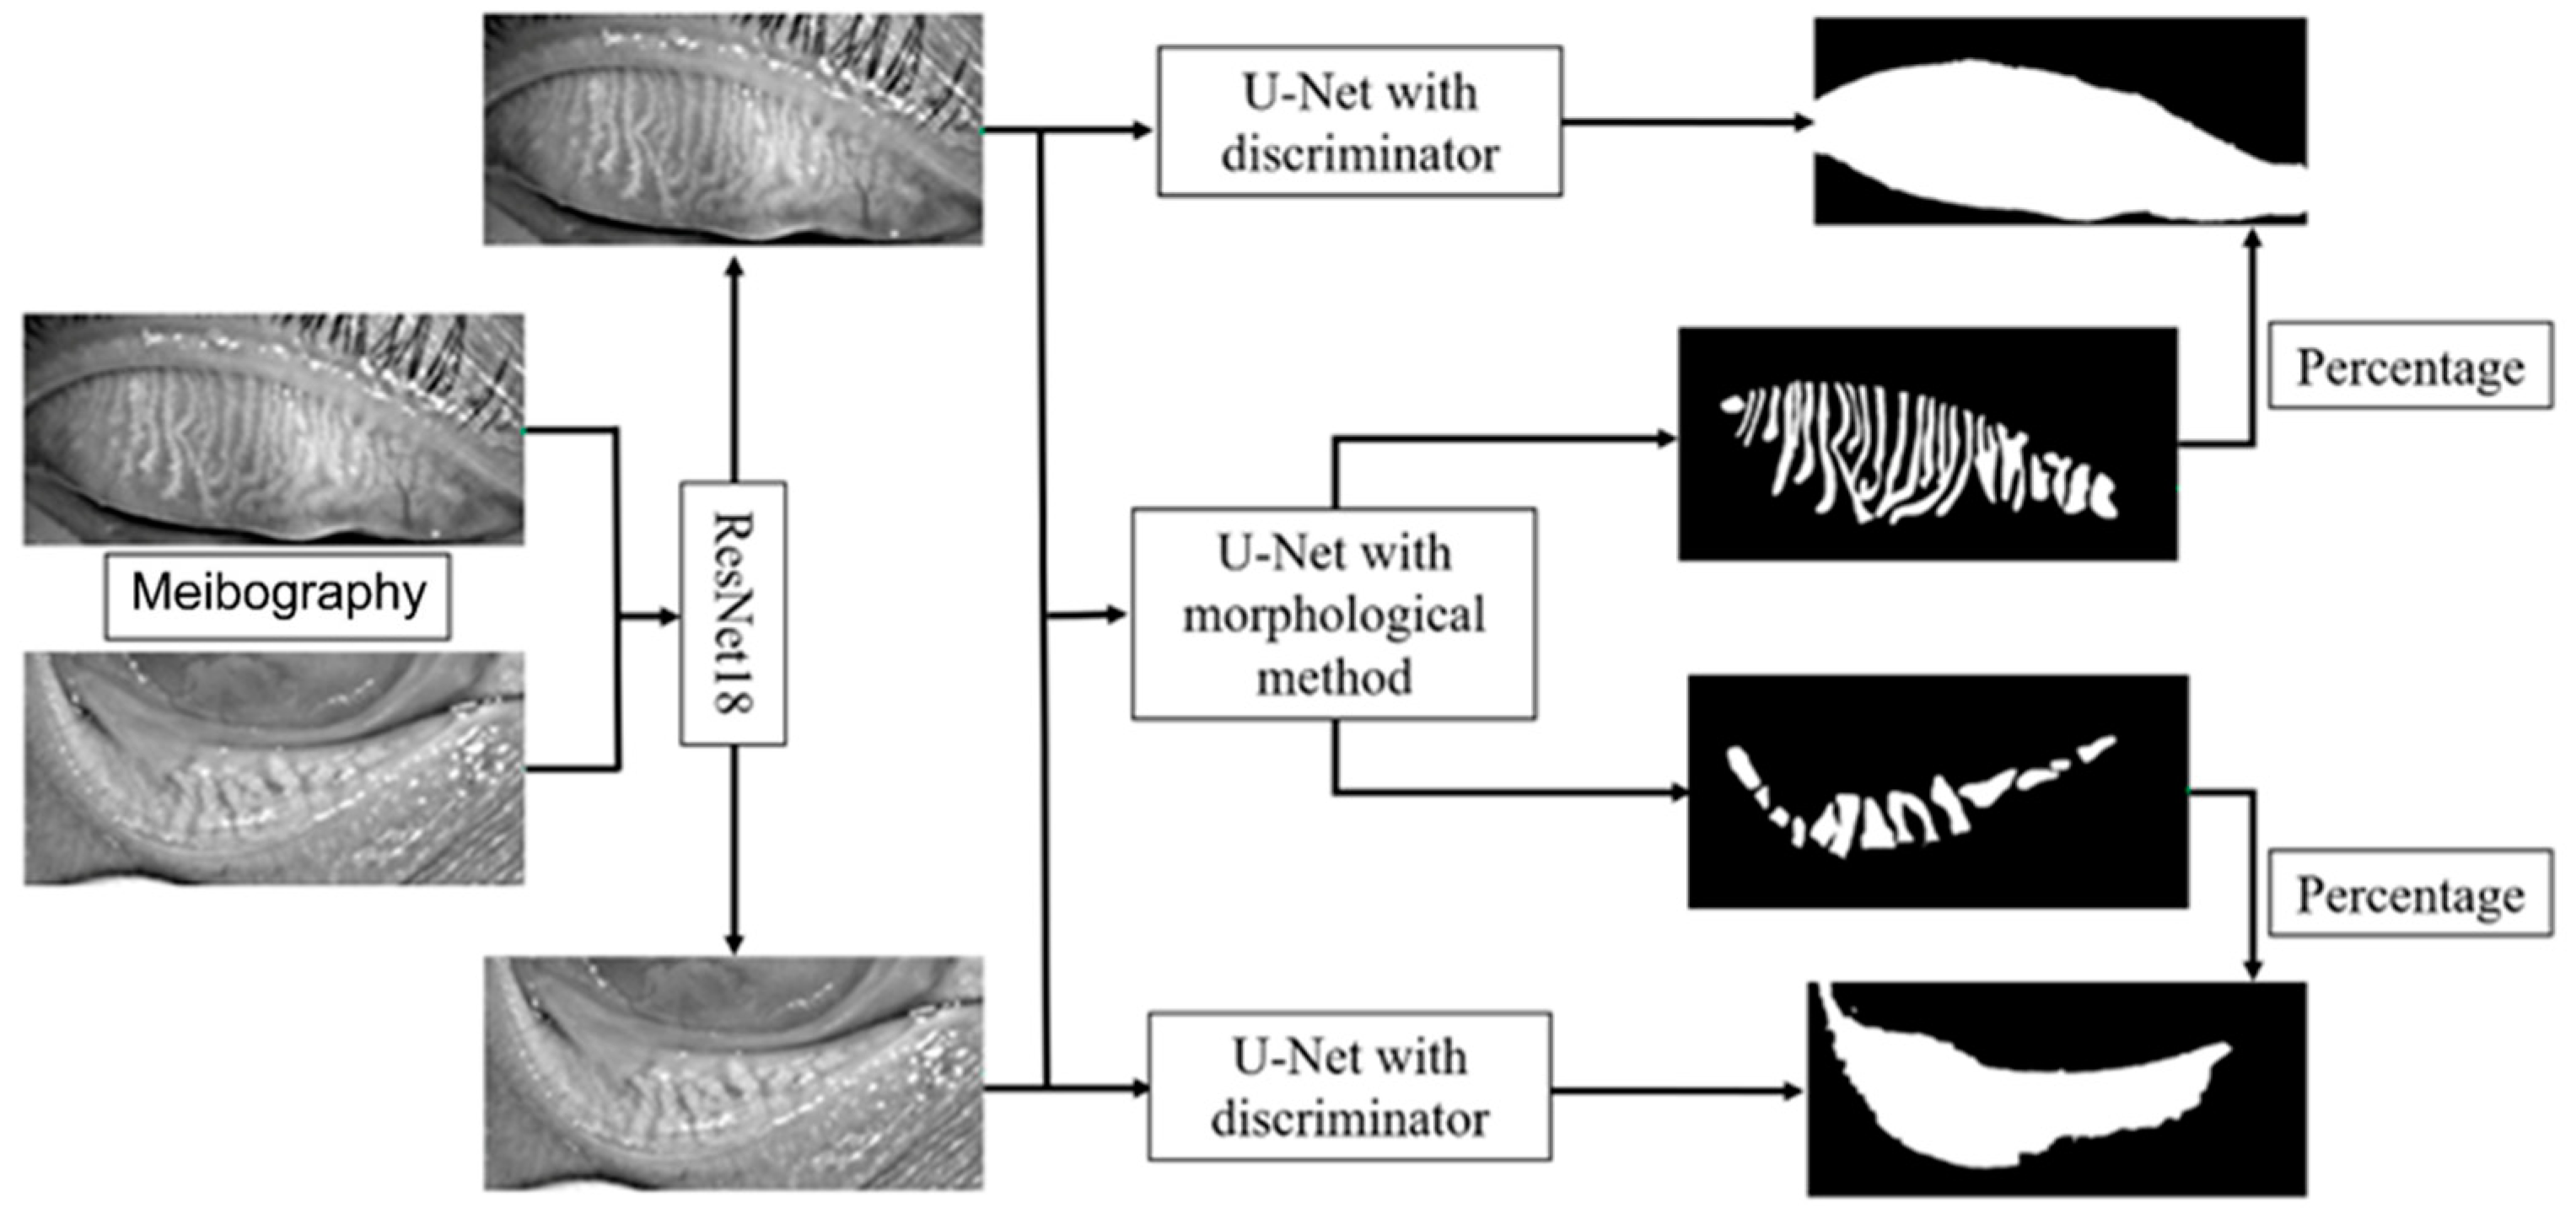

The framework of the deep learning model is shown in

Figure 2. The model mainly consists of three parts, the upper and lower eyelid classifier, tarsus area segmentation, and meibomian gland segmentation. We first trained a ResNet18 model to classify the image as the upper or lower eyelid to achieve a more accurate segmentation based on the morphological characteristics of the upper and lower eyelids. The ResNet18 model leveraged 18 convolution blocks and the last binary classifier layer, which can effectively extract different features in the upper and lower eyelids and implement classification.

We employed a convolutional network model based on U-Net to segment the tarsus and meibomian glands. The normalized image was passed to an encoder transferred from ResNet34 to extract the feature, and then a segmentation decoder was employed, which could upscale the feature map to the same size as the original input image and implement the tarsus region. The skip connections also were used to promote the transmission of low-level features to higher levels. Another reconstruction decoder was cascaded after the feature extractor encoder to reconstruct the feature map to the original image so that we could help the encoder extract a more accurate feature map by the backpropagation of the error between the input image and the reconstructed image. More importantly, we imported the discriminator with fixed parameters from the pre-trained VAE-GAN as a quality inspector, embedding the shape constraint information into the neural network.

The tarsus region has a relatively definite shape. A VAE-GAN model was applied to extract and learn the shape feature. Then it could help the U-Net model to segment the tarsus region having a shape similar to the learned shape feature, as shown in

Figure 3. In the VAE-GAN, the encoder and decoder formed a stacked autoencoder, which encodes tarsus images (Ground Truth, GT / Real) manually labeled by human experts into a feature space represented by a hidden vector Z, which is passed to the decoder for randomly generating eyelid tarsus images (Fake). Finally, the prior knowledge of the shape of the tarsus region is embedded in the convolutional neural network by training the discriminator of the real tarsus and fake tarsus. Here, the generator (G) and discriminator (D) formed a Generative Adversarial Network (GAN), and they increased the sensitivity and discrimination of the discriminator to the specific shape of the tarsus region in the process of fighting each other.